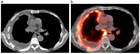

1. 胸膜中皮腫は壁側胸膜の中皮細胞に初発する難治性腫瘍であり、石綿(アスベスト)曝露と密接に関連して発生する。

1. 胸腔鏡で腫瘍が確認されない最も早期の胸膜中皮腫である”mesothelioma in situ(前浸潤性中皮腫)” の存在は以前から知られていたが、『WHO分類 第5版』に初めて明記された。

1. 早期の胸膜中皮腫と反応性中皮細胞増生(反応性中皮過形成)の病理像は類似し、良悪の鑑別は慎重に行う必要がある。BAP1免疫染色、CDKN2A遺伝子の中皮腫でのホモ接合性欠失の検出が鑑別に役立つ。